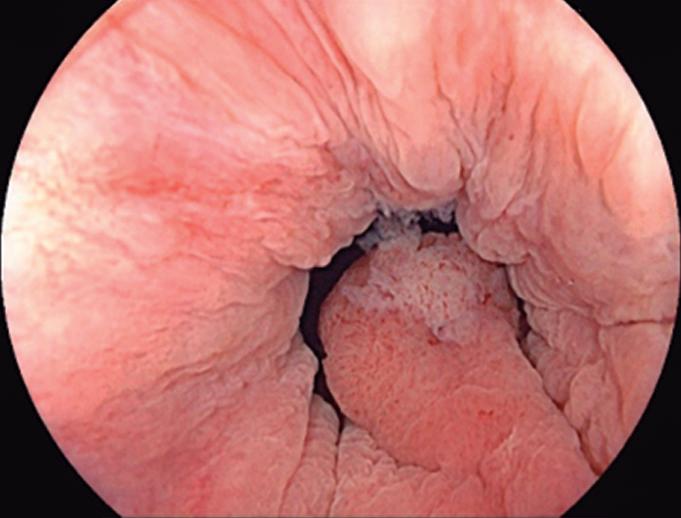

Evaluación endoscópica e histológica

La endoscopía superior es un procedimiento fundamental para el diagnóstico, la evaluación de la respuesta al tratamiento y el monitoreo a largo plazo de la actividad de la EEo. Los hallazgos endoscópicos típicos incluyen edema (reducción de vascularidad), anillos esofágicos fijos, exudados blancos, surcos longitudinales, estenosis, estrechamiento de la luz esofágica, friabilidad de la mucosa (mucosa en papel crepé) y una consistencia firme de la mucosa al realizar biopsias (signo de “tracción" o "resistencia”) en pacientes con fibrosis (Figura 1). Estos hallazgos no son patognomónicos y no constituyen un criterio diagnóstico; sin embargo, cuando se evalúa de forma cuidadosa, en la gran mayoría de los casos se pueden observar.19-21

Es imperativo llevar a cabo una exploración endoscópica minuciosa en todos los casos de sospecha de patología esofágica. En el contexto de la EEo, esto requiere dedicar un tiempo adecuado a la visualización completa del esófago tras la intubación, evitando desplazar o raspar los exudados, insuflando adecuadamente el esófago, eliminando cuidadosamente mucosidad, saliva o detritus, y evaluando el calibre esofágico. Esta evaluación puede incluir la retroflexión en la unión gastroesofágica para estimar el diámetro de las estenosis en dicha región.22

Un elemento fundamental en la evaluación de la EEo es la aplicación del puntaje de referencia endoscópica para la esofagitis eosinofiílica (EREFS por sus siglas en inglés: Eosinophilic Esophagitis Endoscopic Reference Score).20 El acrónimo EREFS también refleja las cinco características endoscópicas principales de la EEo: Edema, anillos esofágicos (Rings), Exudados, surcos longitudinales (Furrows) y estenosis (Stricture). Estas características se clasifican según su severidad mediante un sistema de puntuación que oscila entre 0 y 9, considerándose la región esofágica con la alteración más marcada. El EREFS cuenta con validación interna y externa, y ha demostrado una elevada capacidad para diferenciar la EEo de otras patologías no relacionadas en poblaciones pediátricas y adultas, además de correlacionarse con la respuesta terapéutica.23-25 Por estos motivos, el EREFS constituye un sistema estandarizado para la evaluación

En el panel A se observa un esófago con edema difuso y pliegues longitudinales; en el panel B se aprecia edema con pliegues y exudados blanquecinos; en el panel C se evidencia un estrechamiento luminal acompañado de anillos esofágicos y exudados; y en el panel D se muestra un desgarro mucoso posterior a la dilatación con bujía de Savary, hallazgo esperado tras este procedimiento terapéutico.

Figura 1. Características endoscópicas de la esofagitis eosinofílica